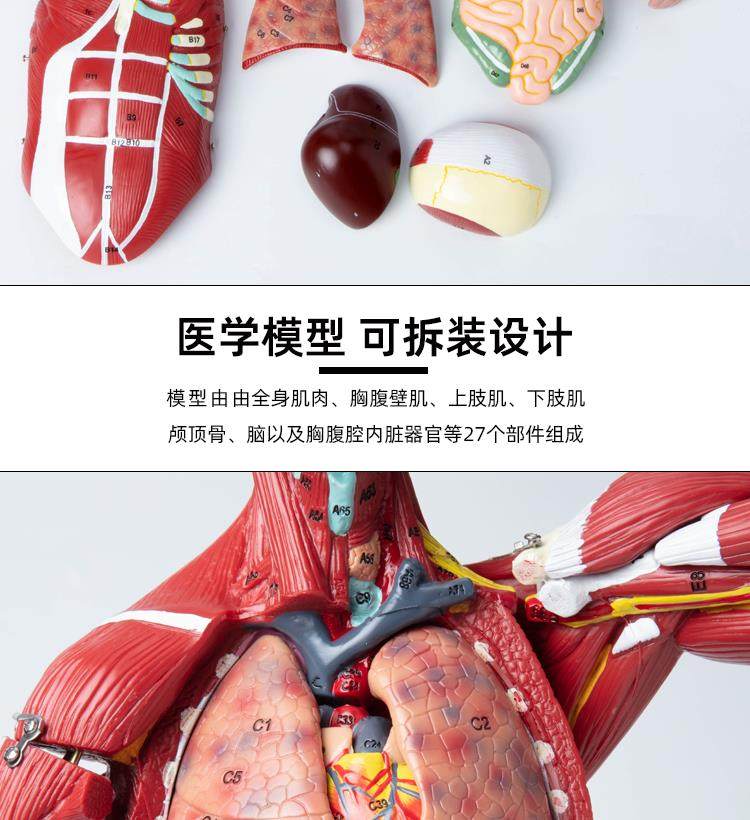

Human Body Muscle Internal Organ Disassembly Anatomy Structure Model Tissue Exercise Artificial Medical Teaching Aids

| Color Classification | 85 Human Muscle Internal Organs Removable Organ,50cm Muscle Model |